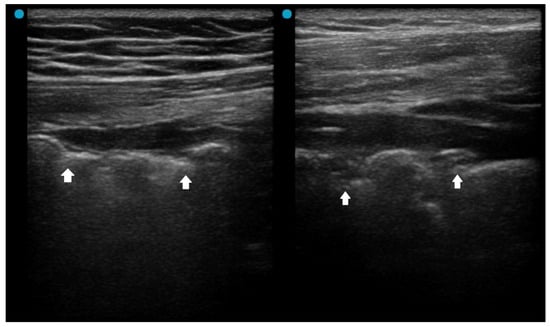

2.2. Red Flag Signs Related to Complicated Pneumonia

Fluid bronchogram is originally described as a sign on CT [23]. It is also described in post-obstructive pneumonia in ultrasonography, identified as anechoic tubular structures with hyperechoic walls but without color Doppler signals (Figure 2) [24,25].

Figure 2. Fluid bronchogram (arrows) in a patient with left upper lobe obstructive pneumonia. Vessels and fluid-filled bronchi can be differentiated with color Doppler (the light yellow box indicates the region of interest box).

Post-obstructive pneumonia with a fluid bronchogram usually reflects complete bronchial obstruction, making the consolidation refractory to antibiotic therapy alone.

The ultrasonographic appearance of pneumonia in children can be used for adults [22]. A study investigating pediatric hospitalized patients found that children with an uncomplicated CAP presented an air, arboriform, superficial and dynamic bronchogram, as opposed to complicated CAP, which had an air and liquid bronchogram, deep, fixed [26]. Another pediatric study reported that fluid bronchogram, multifocal involvement, and pleural effusion were associated with adverse outcomes, including longer hospital stay, ICU admission, and tube thoracotomy in hospitalized CAP children [27].